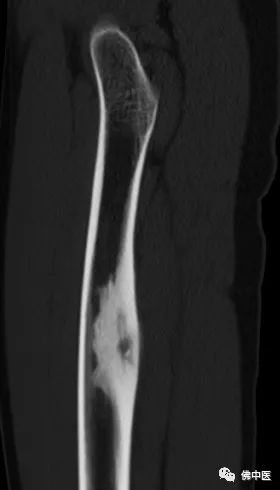

小陆右腿检查片

此为横切面视角

经诊断,小陆同样患有骨样骨瘤。据其主治医生潘海文介绍,经影像学检查,病灶位于大腿中上段内后方,大腿内后方分布有重要的神经血管,加上瘤巢细小,直径仅约7毫米,术中探查犹如大海捞针。